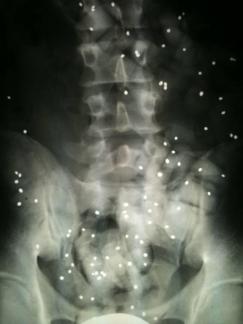

Wie wichtig sind Röntgenbilder?

Röntgenbilder sind wichtig, aber häufig überbewertet.

Wenn keine Hinweise auf eine scherwiegende Erkrankung (spezifische Rückenschmerzen) vorliegen dann ist die genaue Befragung und die Untersuchung wichtiger als Röntgenbilder.

Wenn Sie Röntgenbilder mitgebracht haben werden wir und diese gemeinsam mit Ihnen anschauen.

Nicht selten erwidern Patienten auf die Frage, was sie zu uns führt, mit der Antwort: "Schauen sie die Bilder an, ich habe 3 Bandscheibenvorfälle!".

3 relevante Vorfälle sind selten und solche Aussagen kommen zustande, wenn die Röntgenbefunde fehlinterpretiert werden.

Lesen Sie folgenden Kernspinbefund und Sie sind überzeugt so richtig krank zu sein:

Der Befund kann für einen durchschnittlichen 50jährigen durch 2 Worte ersetzt werden:

Altersentsprechender Befund.

Der Radiologe beschreibt auf den Bildern alles was er sieht, und das sind natürlich auch Verschleißerscheinungen.

Wenn ein Gutachter mein Auto (150.000km) beurteilt, wird ein mehrseitiger Bericht dabei herauskommen. Dass ich aber damit dennoch im Jahr problemlos 30.000km fahre ist davon unbenommen.

Verschleiß ist normal; meistens macht das keine Probleme.

Bei jeder Bewertung eines Befundes ist die Relevanz wichtig. Darum werde ich die Röntgenbilder mit Ihnen besprechen.